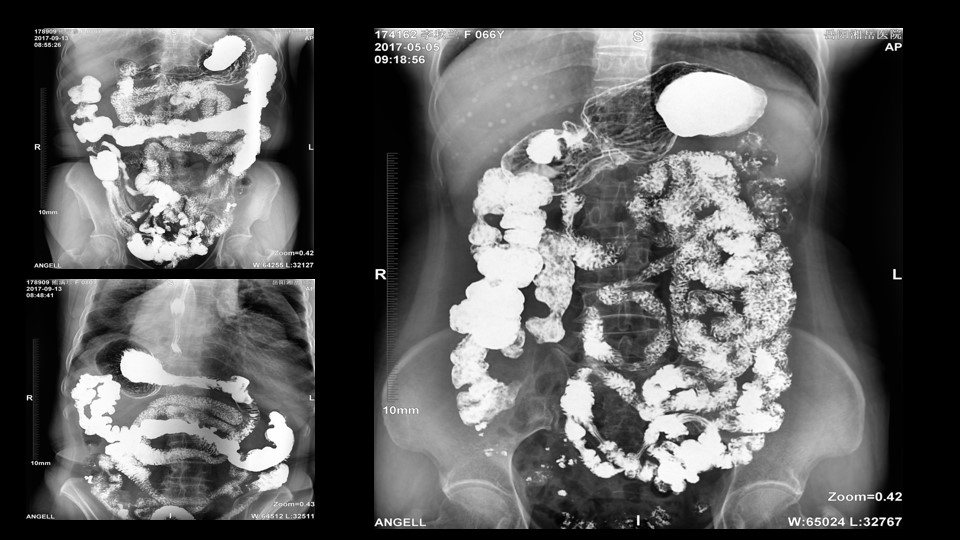

会议开始,岳阳市医学会放射分会副主委、湘岳医院放射科蔡雨主任,结合自身在放射影像的20多年经验,为参会嘉宾分享了动态DR在消化道造影中的应用价值。作为动态DR用户,蔡雨主任结合动态DR的实际拍片与操控经验,分享了动态DR技术在相关群体疾病检查上的独到优势和人文关怀。蔡雨主任说到:“随着内镜技术的发展以及CT、MR的发展,消化道造影在减少,但是这并不意味着消化道造影的价值在下降。以老年人为例,很多老年群体都患有严重的心肺疾病、或者消化道畸形,很多老年人本身就有糖尿病、高血压等等综合疾病,传统内镜的检查对于这类群体来说是一件难以忍受的痛苦,而动态DR的多项创新技术让这类群体的消化系统疾病筛查变得更为人性和精准。任何一个好的消化道造影,一定是患者、诊断医生、临床医生三方满意的结果。亿万28入口网页版-亿万28网页在线玩-万28官网下载最新版-亿万e网址pg-亿万28pg电子-亿万28赏金女王-亿万28娱乐科技动态DR技术利用900万像素高清拍片、大幅面透视、高清点片、视频保存与回放等核心功能,完全满足临床对消化道气钡双重造影检查的需要。图像质量全面超越以往模拟胃肠机、影增数字胃肠机”。蔡雨主任全面演示了动态DR在食道造影、上消化道造影、小肠双对比造影、结肠气钡双对比造影中的应用,通过动态DR可以清晰获得临床诊断和评估的图像依据。

蔡雨主任使用动态造影图像示例